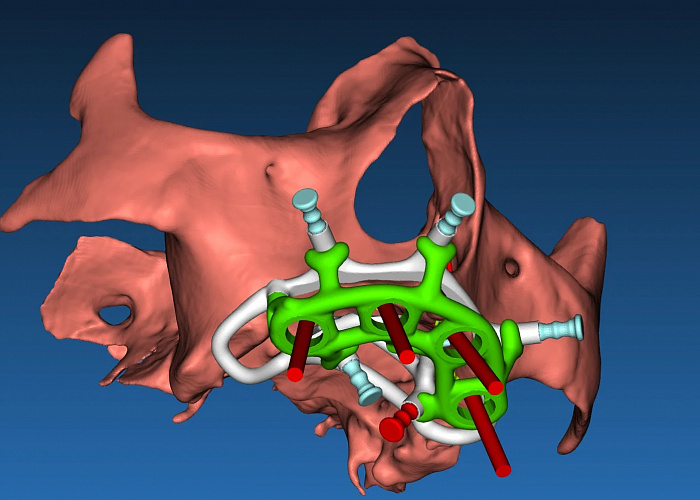

Планирование хирургического шаблона используя RealGuide

Санкт-Петербург, улица Седова, 11к2

Стоимость:

31 000 ₽

Организатор: Вилана

Лектор: Мазлум Махмуд Мохамедович